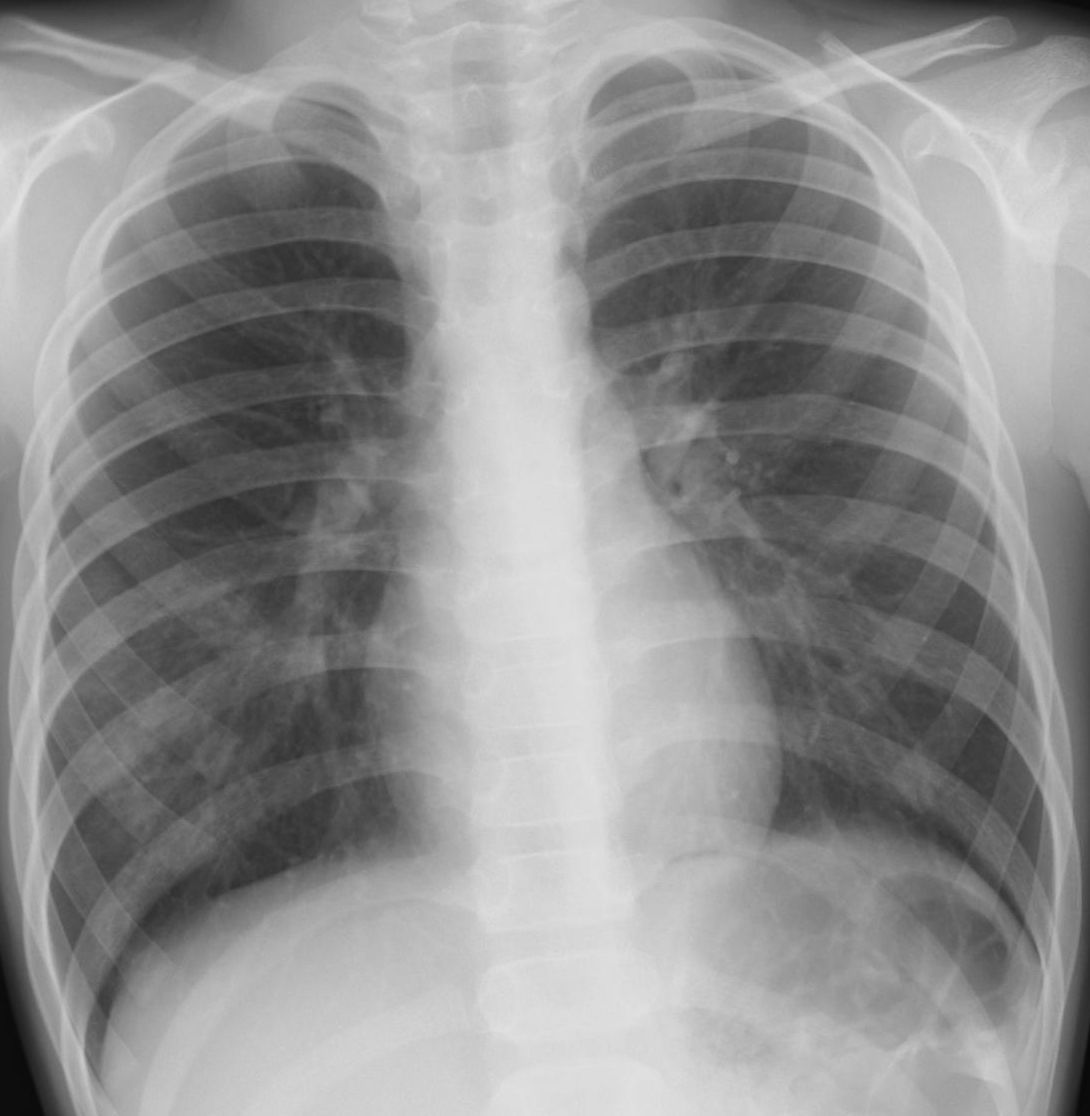

外来でよくみられる肺炎、マイコ・クラミジア・肺炎球菌・ウイルス(RSウイルス・hMPV・インフルエンザウイルスA・B)について実際に経験、外来で治癒した症例を提示します。軽症な変化のものが大多数ですが中には重症なものも紛れていて、注意が必要になります。

【マイコプラズマ肺炎】

胸部写真の読み方